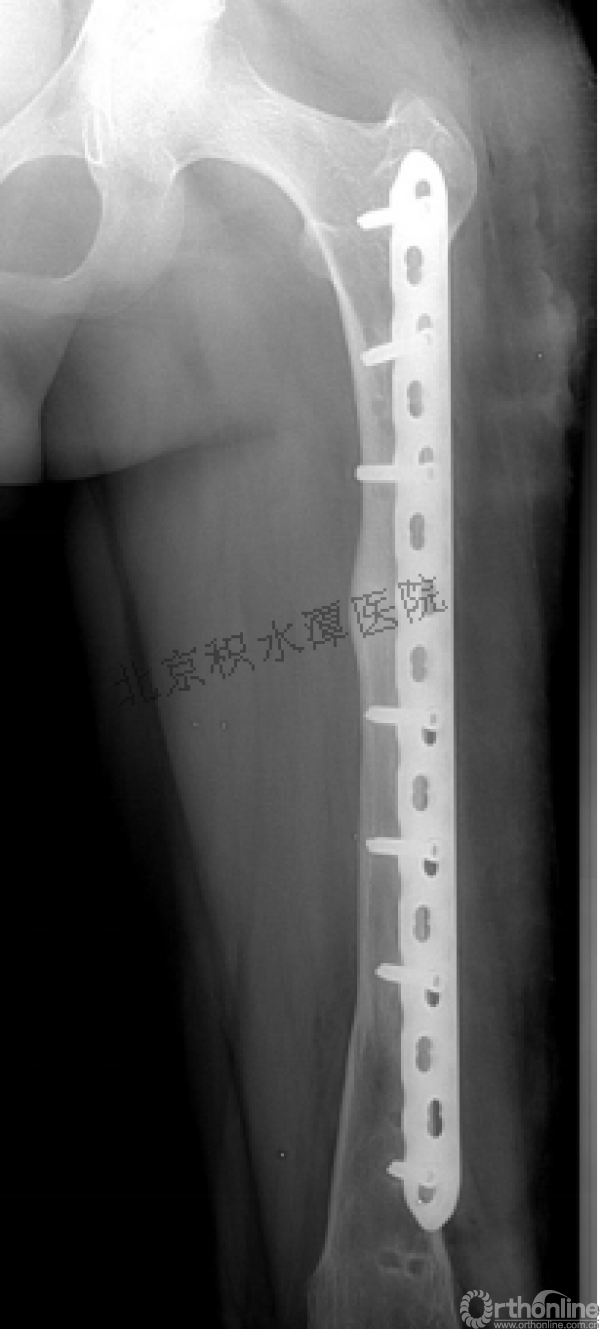

病例分享六

7岁、男孩,桡骨远端骨折

原始损伤片

手法整复后 - 45分钟!

伤后4天复查

伤后30天!

医生的处理方法!——医生终于没有坚持自己的原则!

伤后40天—切开复位内固定!

伤后18个月

如何面对?

心情之压抑无以言表!

手术历时近 5小时!心情之压抑无以言表!因为当时的经治医生是他们的进修生!感觉是他们的失职甚至渎职!

唯一可以肯定—预后不佳!郭教授是党员!是无神论者!但是很诡异的事情:手术中发生—C形臂看不清!拍片条件总是调节不好!手术器械换了三套!内固定钢板总不合适!

术后15月,虽然家长满意了,但是他们医生不满意!